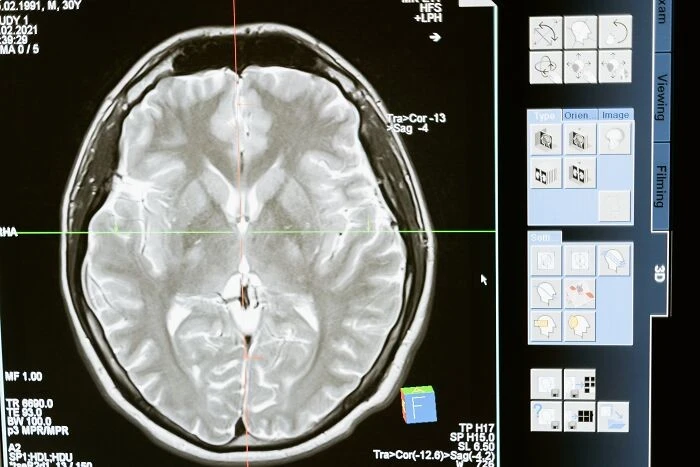

11. «Если ствол головного мозга (часть мозга, которая отвечает за моторный контроль всего тела) поврежден, может развиться синдром «запертого человека». То есть, человек полностью в сознании и осознает свое окружение, но не может двигаться или говорить. Единственные мышцы, которые остаются незатронутыми у большинства людей, — это мышцы, которые двигают глазами и веками. Вы, по сути, заперты в собственном теле, и единственным способом общения является моргание или движение глаз. Это может быть вызвано токсинами, закупоркой основной артерии, которая является основной артерией мозгового ствола, или другим повреждением ствола мозга».

16. «Даже малейшая травма мозга может изменить всю твою жизнь. В зависимости от того, какая часть мозга пострадала, можно лишиться особых/основных чувств, контроля над собственным телом, способности использовать и/или понимать язык, воспоминаний, личности и т. д. Не забывайте надевать шлем, люди!».